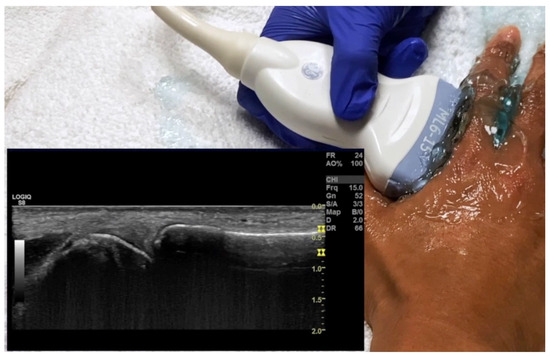

4.2. Evaluation of the Wrist

4.2.2. Volar Aspect